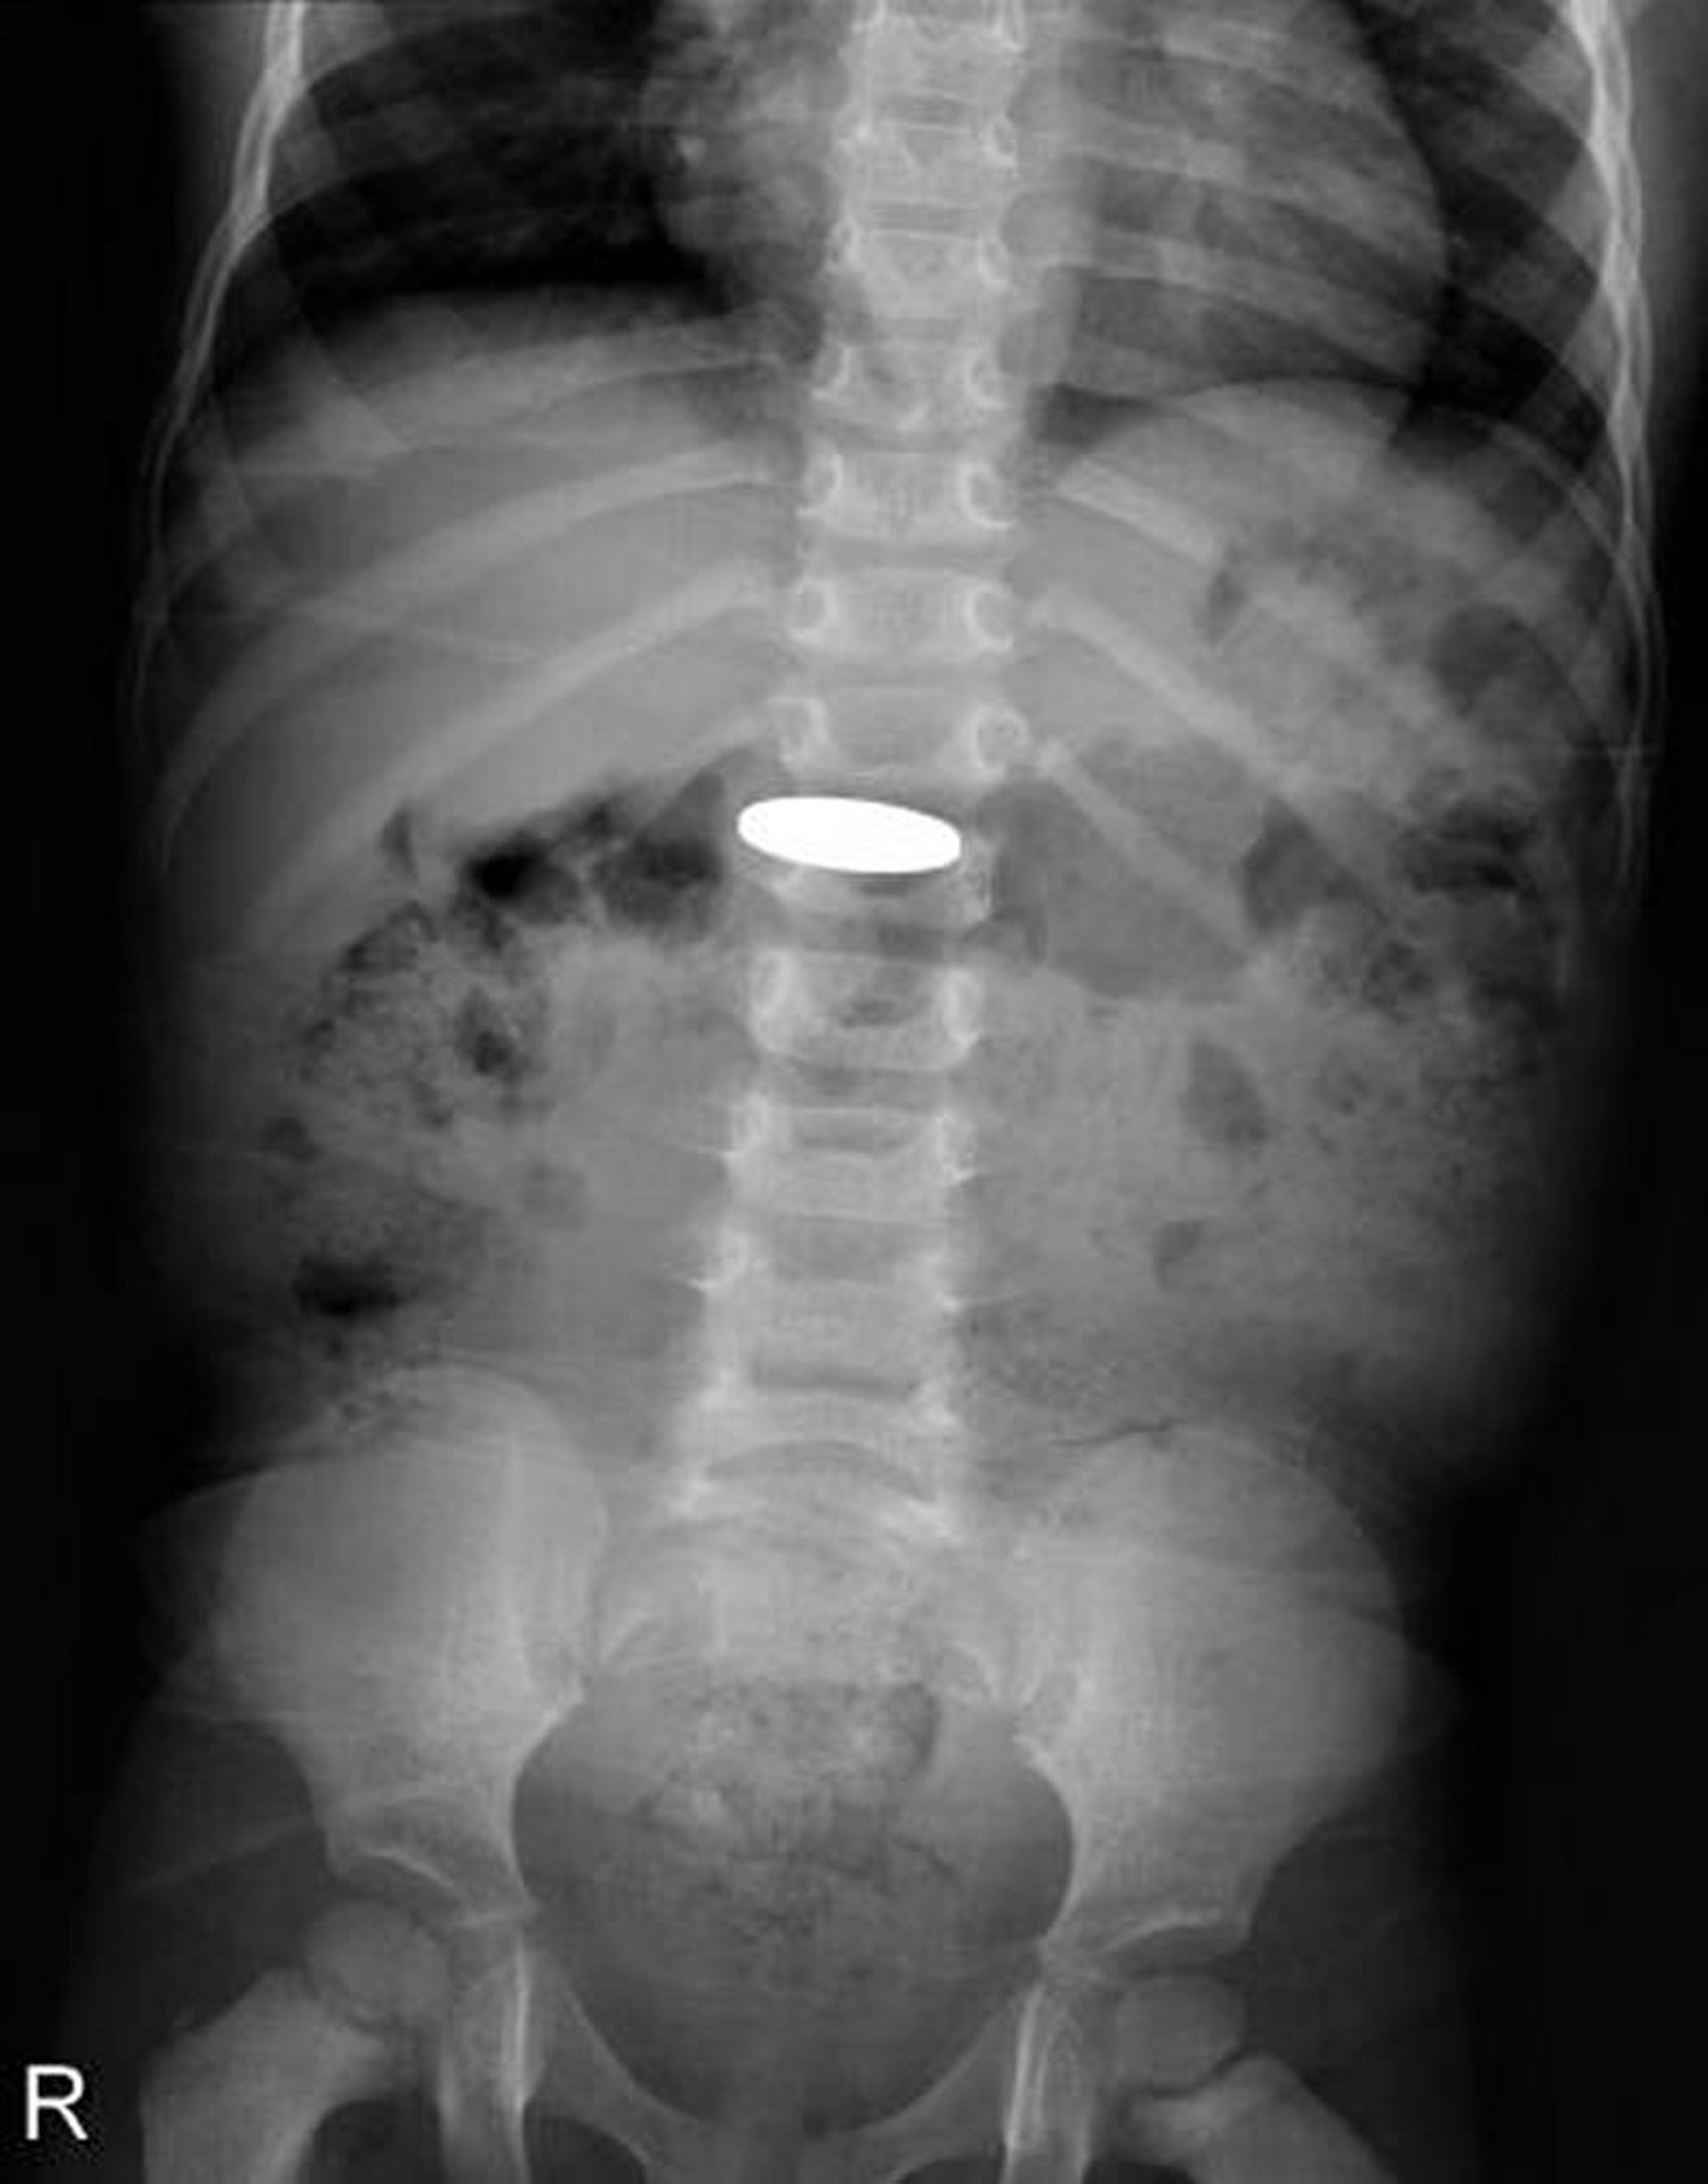

تُظهر هذه الصورة الشعاعية عملة معدنية قام طفل صغير بابتلاعها.